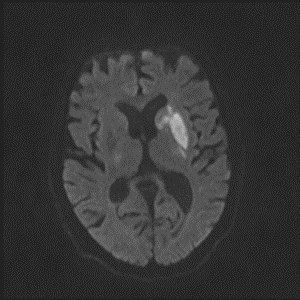

5/ Because the lesion is calcified and suspected to represent ruptured plaque, they are loaded with ASA/Plavix and admitted for close monitoring. MRI shows small infarct: